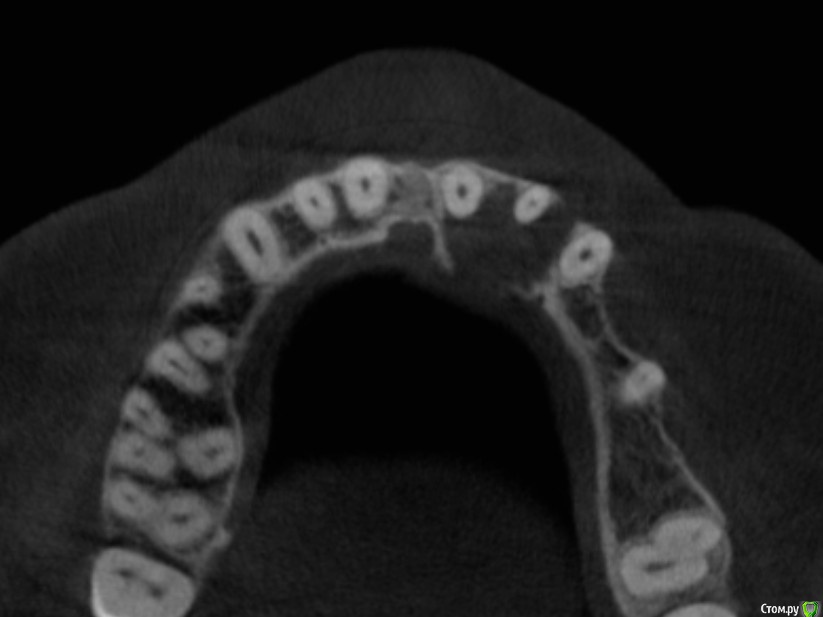

Рустам Опубликовано 17 января, 2016 Поделиться Опубликовано 17 января, 2016 Добрый вечер коллеги! Обратилась пациентка с жалобами на наличие свища в области 22 зуба. Сделали КТ, обширный очаг в области 21, 22. Как считаете, можно попытаться в данной ситуации обойтись консервативным лечением, без хирургии? Ссылка на комментарий

Ico Опубликовано 18 января, 2016 Поделиться Опубликовано 18 января, 2016 ппц,то к рисунку Кости. По тактике: даже если бы результата с Са и не было,не понимаю зачем фистула? Почему не сделать прокол,промыть каким нибудь декасаном и аспирировать? Ну или хирургия.Ром,может и поможет,а если опять свищ,а если опять контоминация в полости и весь процесс по новой.Опять разрез,опять рубец.В данном кеисе с двух сторон нет кортикалки,поэтому такие дефекты очень долго могут заживать. Ссылка на комментарий